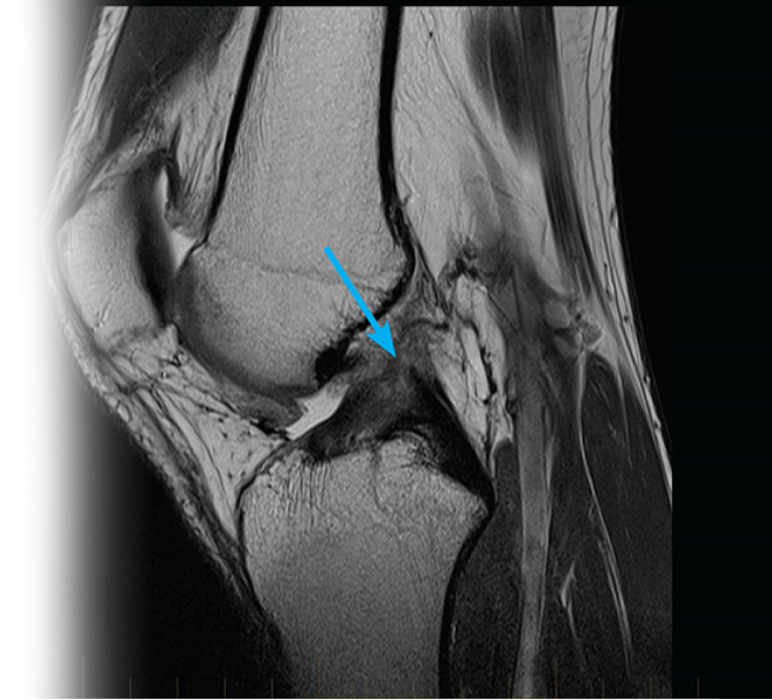

Магнитно-резонансная томография коленного сустава – важный метод исследования, который позволяет визуализировать мениски, крестообразные связки, жировые тела, надколенник, подколенную область, коллатеральные связки, кости, образующие коленный сустав.